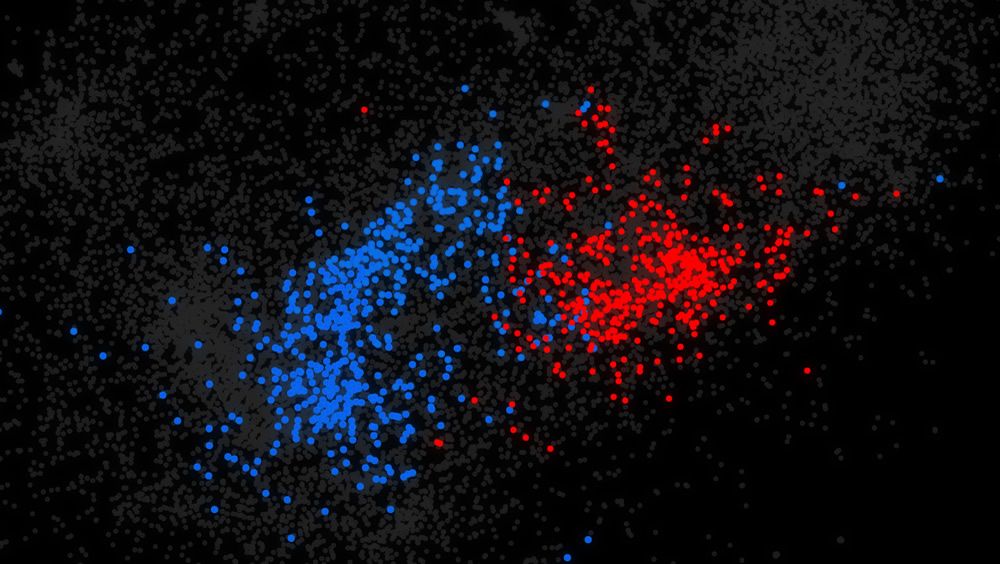

Publicando el 27 de mayo en la revista científica Nature Genetics, los expertos analizaron los genomas de 1.790 familias en las que un niño tiene trastorno del espectro autista (TEA), pero otros miembros no. El método clasificó entre 120.000 mutaciones para encontrar aquellas que afectan el comportamiento de los genes en personas con autismo. Aunque los resultados no revelan las causas exactas de los casos de autismo, revelan miles de posibles contribuyentes que los investigadores pueden estudiar.